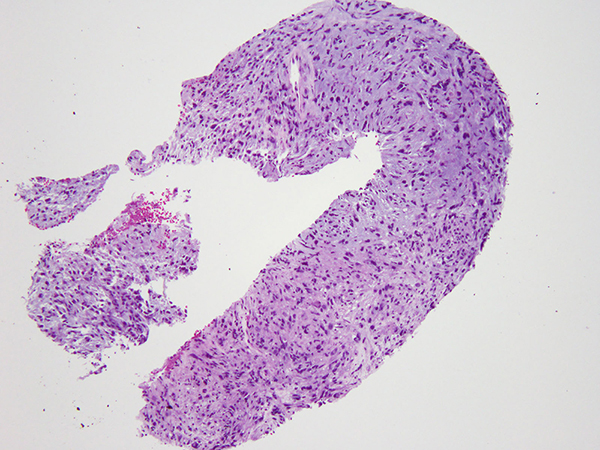

Grossly, PPMS is nodular and well-circumscribed with a pale gelatinous and grey-white cut surface. It ranges in size from 1.5 to 4 cm and is always related to a bronchus with most cases showing a predominant endobronchial component. Microscopically, PPMS is lobulated, often multinodular, and composed of cords of polygonal, spindle and stellate cells with a prominent myxoid lightly basophilic stroma, which is Alcian blue-positive and hyaluronidase sensitive. Occasionally, prominent surrounding fibrosis or fibrous pseudocapsule can be seen, and the associated peritumoral inflammation is generally mild. Focal pleomorphism can be seen and up to 50% of the cases have necrosis. Mitotic activity is generally low with less than 5 mitoses per 10 high power fields.

The tumor is positive for vimentin and can be focally positive for EMA by immunohistochemistry. Focal staining with myoid, neuroendocrine and melanocytic markers has been reported. The defining feature is t(2;22)(q33;q12) chromosomal translocation resulting in the fusion of the EWSR1 and CREB1 genes. Other members of the CREB family transcription factors have also been implicated, including ATF1 and CREM.